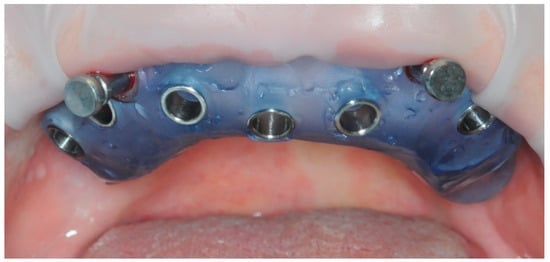

2.4. Temporary Prosthesis

2.5. Final Prosthesis